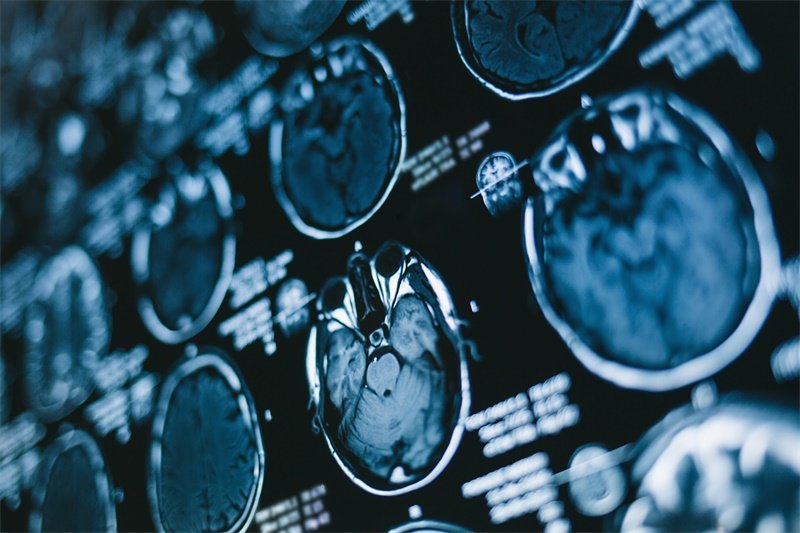

在医疗实践中,核磁共振成像(MRI)是诊断骶骨脊索瘤的主要工具之一。通过MRI,我们能够详细观察到肿瘤的形态、大小及其与周围组织的关系,这对于制定治疗方案至关重要。

MRI是一种非侵入性影像学检查方式,利用强磁场和无线电波生成身体内部结构的详细影像。与其他影像学检查如CT相比,MRI对软组织的成像优势明显。它能够更清晰地显示出骶骨脊索瘤的边界和其对周围组织的侵犯程度。

骶骨脊索瘤在MRI上的表现通常为低信号至高信号的病变。在T1加权像上,肿瘤呈现低信号;而在T2加权像上,通常会显示为高信号,这使得医生可以通过对比不同序列的影像来评估肿瘤的性质。

此外,骶骨脊索瘤的边界通常较为清晰,但在某些情况下,肿瘤可能对周围的骨组织造成浸润性破坏。这种特征在影像学上表现为骨质破坏区域的出现,进一步增强了对肿瘤性质的识别能力。

相对于CT检查,MRI针对软组织的显示更加敏感。因此,在发现骶骨区域有肿块或者症状不适时,MRI成为了首选的影像学检查手段。而CT虽然在骨质破坏的显示上具有优势,但在软组织肿瘤的边界识别和侵犯情况评估上有所欠缺。